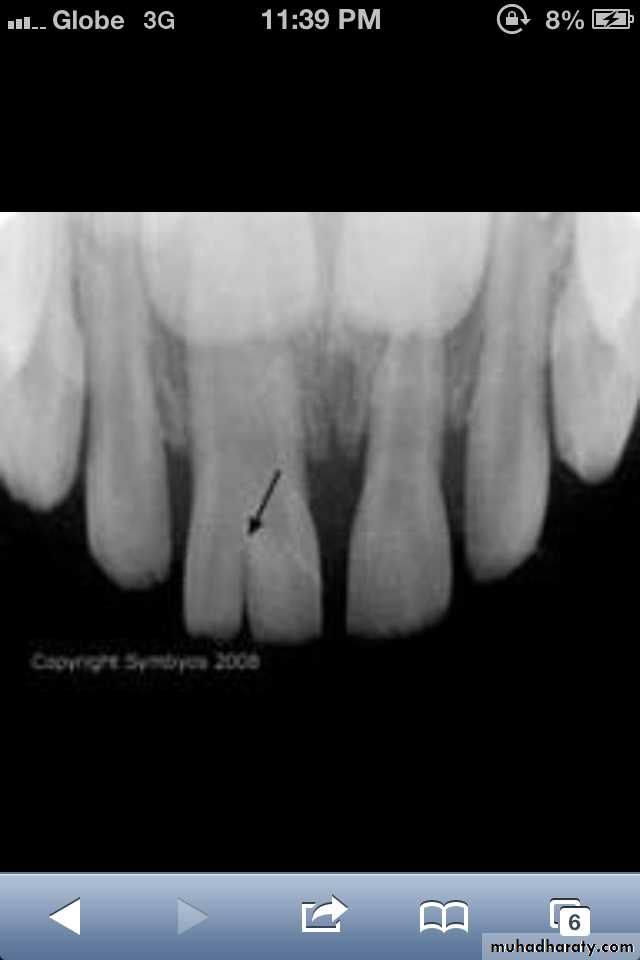

Dilaceration of the crown

specimenX-Ray

Dilacerated root. The apical portion of the root is bent buccally or lingually into the plane of the central ray. Note the halo in the apical region, produced by the PDL

space (arrow).